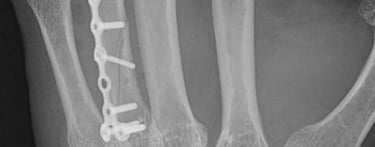

Fracturas y secuelas